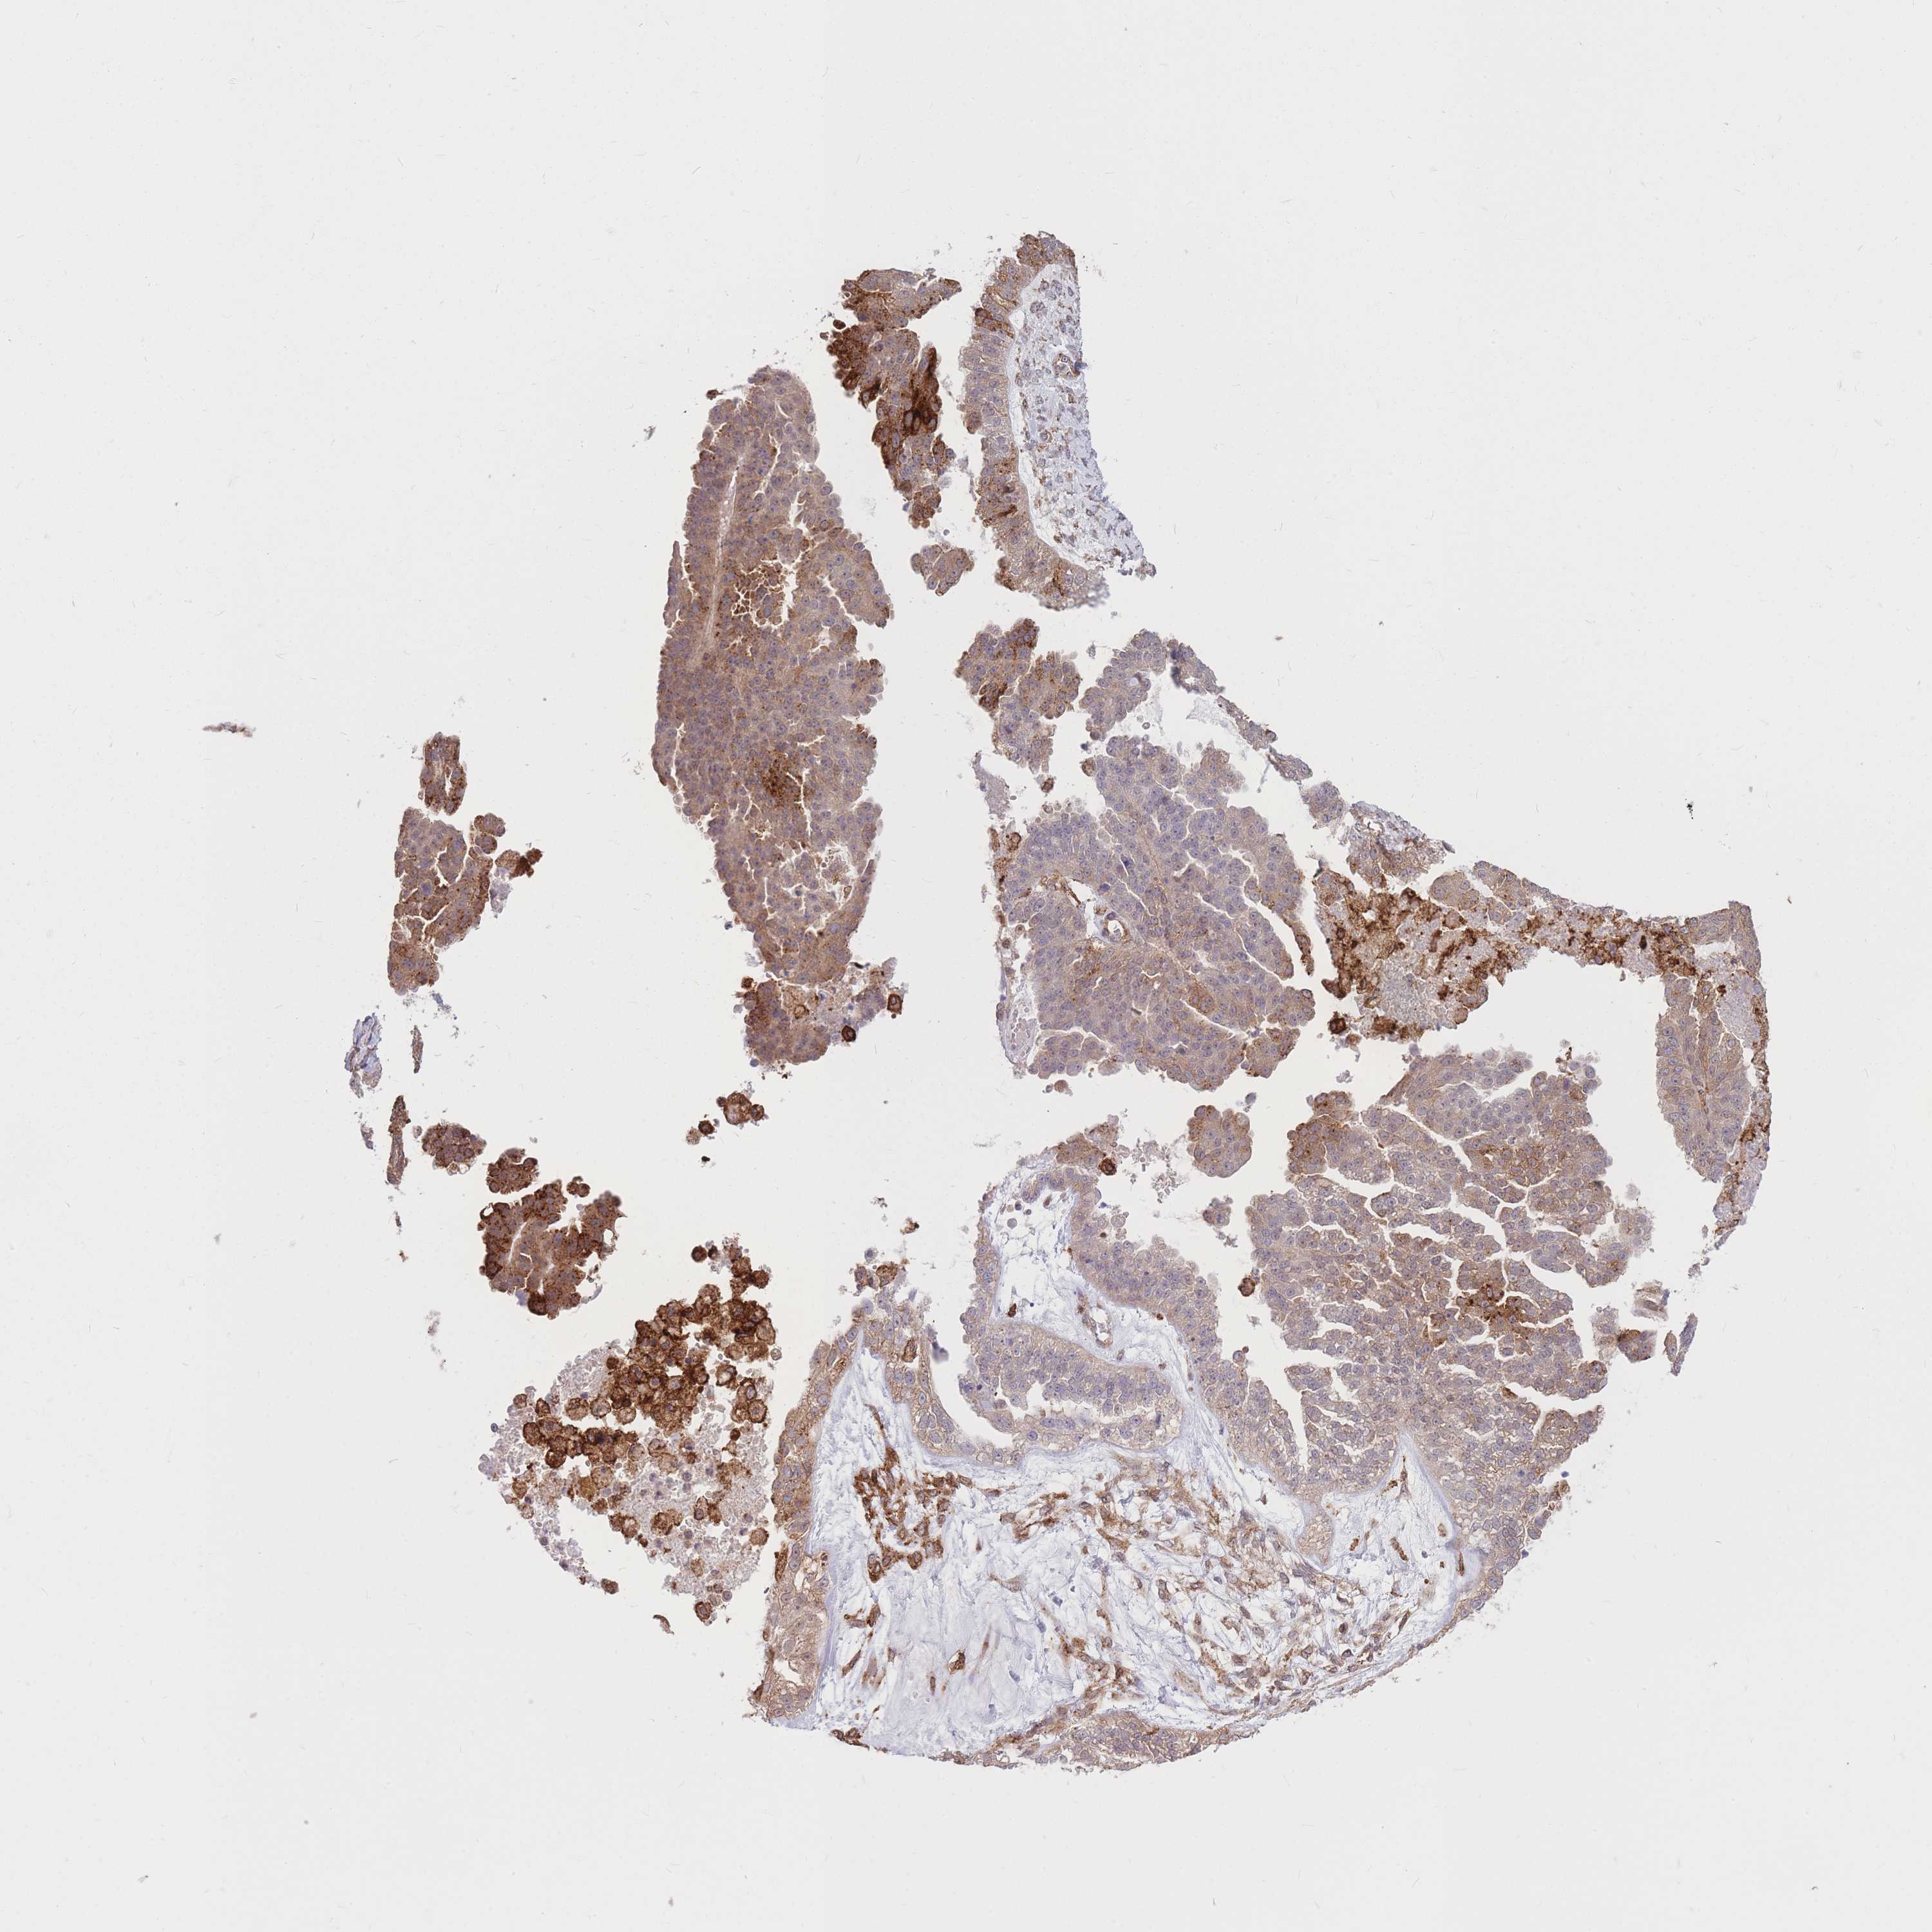

OVARIAN CANCER - Protein expressioni

A mouse-over function shows sample information and annotation data. Click on an image to view it in a full screen mode. Samples can be filtered based on level of antibody staining by selecting one or several of the following categories: high, medium, low and not detected. The assay and annotation is described here.

Note that samples used for immunohistochemistry by the Human Protein Atlas do not correspond to samples in the TCGA dataset.

Antibody stainingi

Antibody staining in the annotated cell types in the current human tissue is reported as not detected, low, medium, or high, based on conventional immunohistochemistry profiling in selected tissues. This score is based on the combination of the staining intensity and fraction of stained cells.

Each image is clickable and will lead to virtual microscopy that enables deeper exploration of all samples and also displays staining intensity scores, fraction scores and subcellular localization as well as patient and tissue information for each sample.

Antibody HPA036786

Antibody CAB017849

Cystadenocarcinoma, serous, NOS